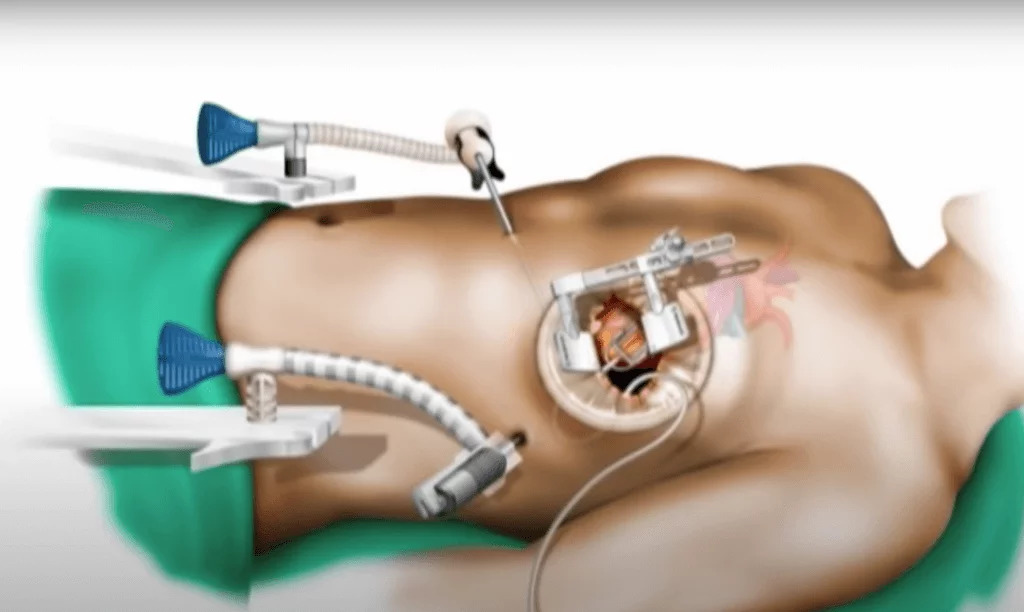

Open Heart Surgery

Coronary Artery Bypass Grafting (CABG) is a surgical procedure performed to treat blocked coronary arteries. A healthy blood vessel from the body is grafted to bypass the blocked artery, improving blood flow to the heart muscle and reducing cardiac risk.